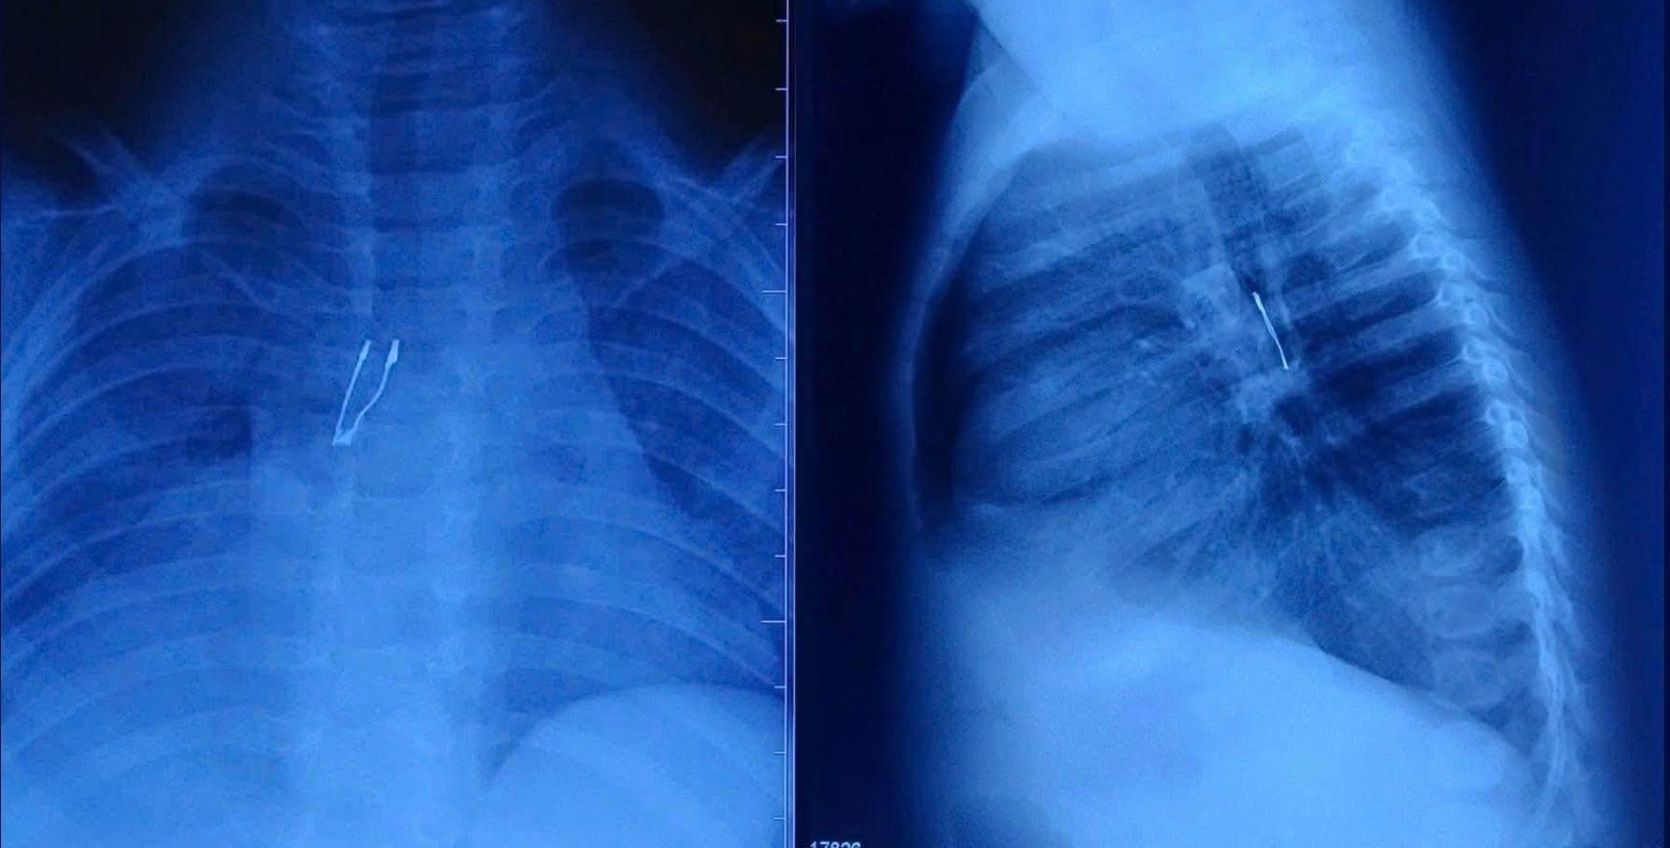

X-ray results showed that the contrasting foreign object was located in the right root bronchi, accompanied by signs of incomplete right lung collapse and mediastinal pneumothorax. These are complications showing that the situation is not simple. The Ear, Nose and Throat Department team consulted and coordinated with the anesthesia team to perform emergency airway endoscopy for the baby.

According to BS.CKI Ly Pham Hoang Vinh - Department of Ear, Nose and Throat, Children's Hospital 1, the foreign object is suspected to be a LED light bulb located deep in the root right bronchi. The biggest difficulty in the foreign object removal process lies in the structure of the light bulb: the bulging, sharp tail, easily stuck when pulled through the larynx, posing a potential risk of scratching, tearing the mucous membrane or getting stuck between the 2 vocal cords.